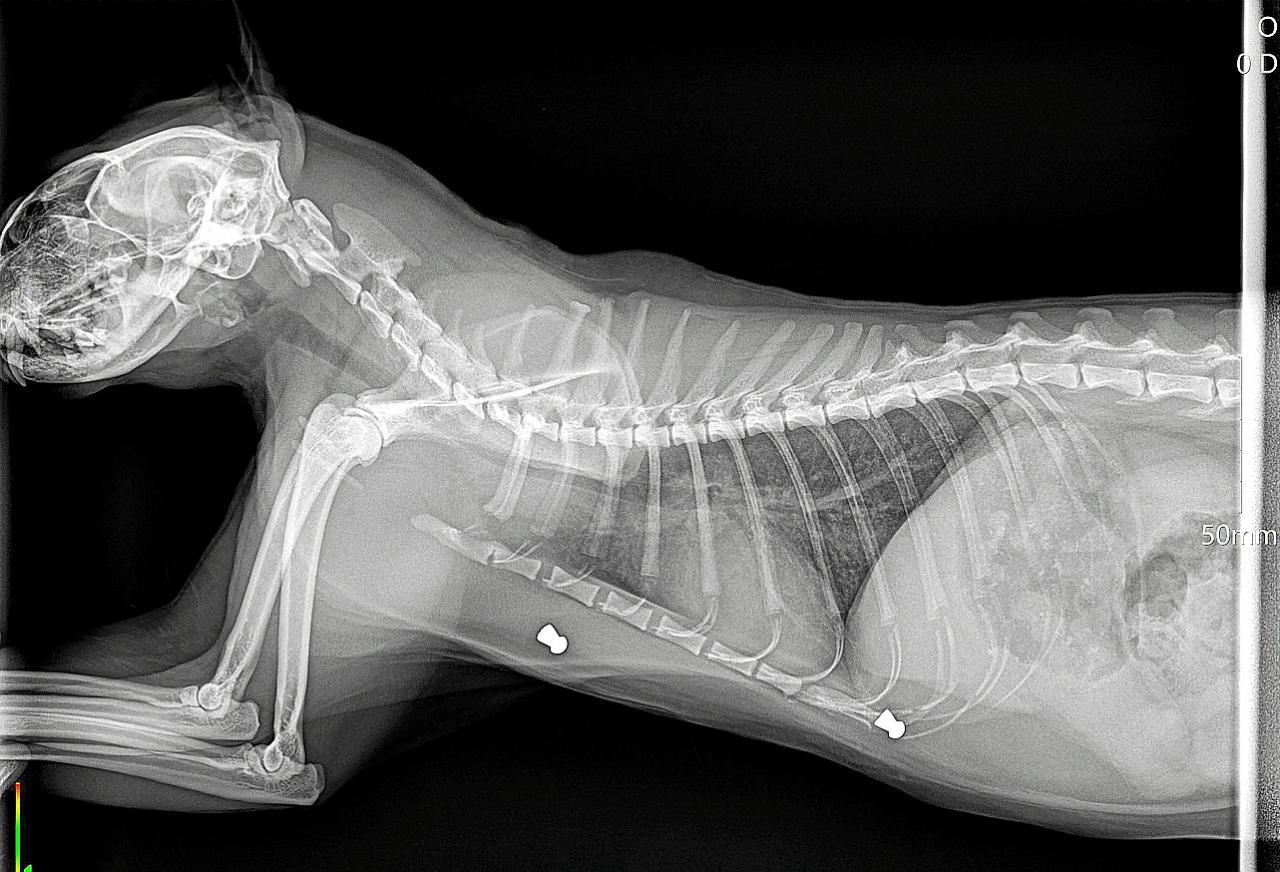

The Guardia Civil's Seprona division are investigating a number of suspects in connection with the shooting of cats in Cala Murada, Manacor.

Guardia Civil investigating the shooting of at least 50 cats

The shootings started in October 2019